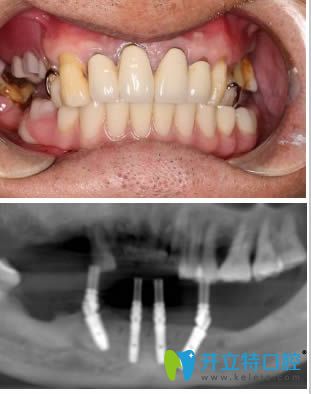

術(shù)后影像及半口即刻種植牙一年后的樣子:

經(jīng)過這次種植牙經(jīng)歷,說心里話,我有點(diǎn)后悔.....后悔沒有在早些年來做種植牙,害的我遭受了戴假牙的后遺癥。自從種做完半口種植牙后,吃蘋果、啃排骨真是和真牙一樣,想吃什么吃什么.....這一年以來,讓我享盡了口福啊。